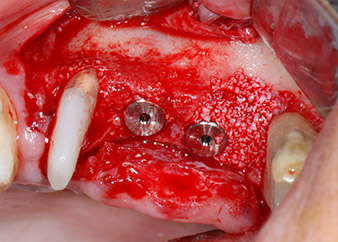

Les lits implantaires ont été préparés sur les sites 25 et 26 à l'aide d'instruments rotatifs, utilisés dans un contre-angle avec un rapport de transmission 20:1 avec un nouveau moteur d'implantologie puissant (Implantmed, W&H) (Fig. 8).

Les implants (Restore, Keystone Dental, 3,75 mm de diamètre, 8,0 mm de long) ont été mis en place à l'aide du moteur d'implantologie (Fig. 11 et 12).